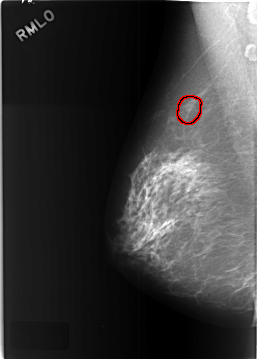

C_0449_1.LEFT_MLO

LEFT_MLO LINES 5768 PIXELS_PER_LINE 4120 BITS_PER_PIXEL 12 RESOLUTION 50 OVERLAY

FILE: C_0449_1.RIGHT_MLO.OVERLAY

TOTAL_ABNORMALITIES 1

ABNORMALITY 1

LESION_TYPE MASS SHAPE ROUND MARGINS CIRCUMSCRIBED

ASSESSMENT 3

SUBTLETY 3

PATHOLOGY BENIGN_WITHOUT_CALLBACK

TOTAL_OUTLINES 1

BOUNDARY